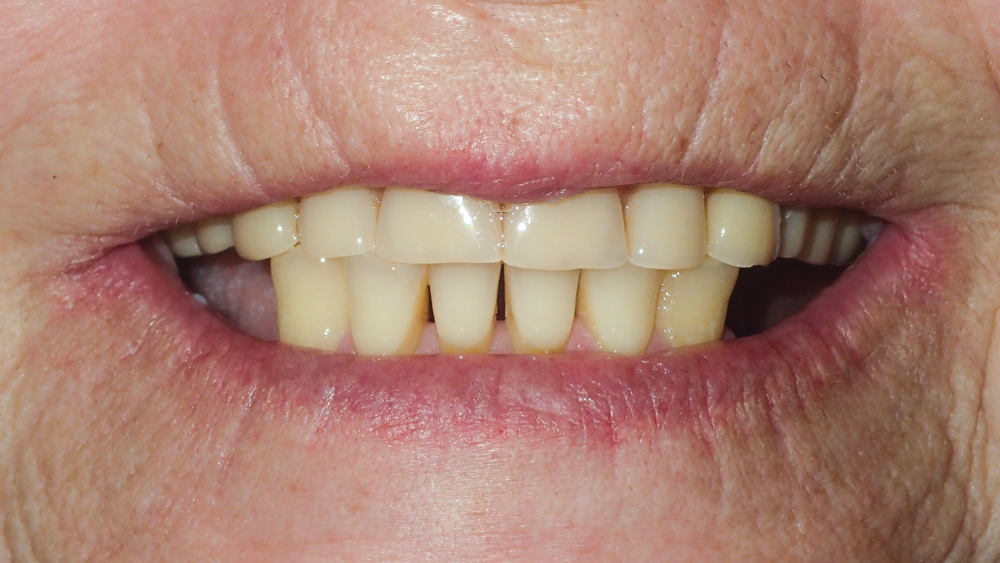

This patient was unhappy with the esthetics of her existing upper denture as well as the discomfort and instability caused by her loose-fitting mandibular partial denture. Although her concerns with the maxillary denture could be addressed with a new, more esthetic appliance, she preferred implant treatment for her mandible, where a fixed solution was needed to adequately restore function, stability and comfort.

The patient’s remaining mandibular teeth were extracted followed by immediate implant placement and delivery of a fixed provisional appliance. After integration of the implants, the prosthetic designs for the new upper denture and lower implant restoration were determined in tandem. Ultimately, the dual-arch restorations addressed the functional and esthetic challenges of the case while staying within the financial means of the patient, demonstrating the benefits of a flexible, multifaceted approach to restorative dentistry.

The dual-arch restorations addressed the functional and esthetic challenges of the case while staying within the financial means of the patient.